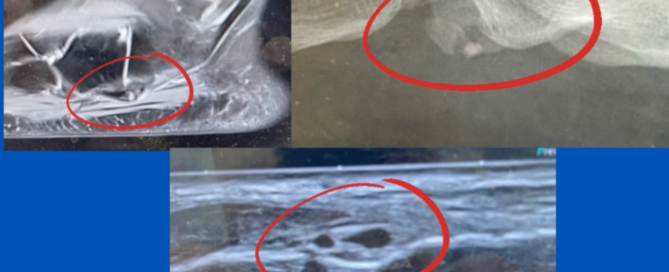

Bipartite Os Peroneum

Blog's main page Approximately 10% of the population have Os Peroneum, an accessory bone in the peroneus longus tendon. It is typically located adjacent to the cuboid as the tendon [...]